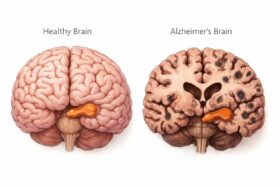

Essa Droga do Alzheimer

Existem idosos com mais de 90 anos que não sofrem desta maldita doença , como minha mãe, Maria Cecília, 96…